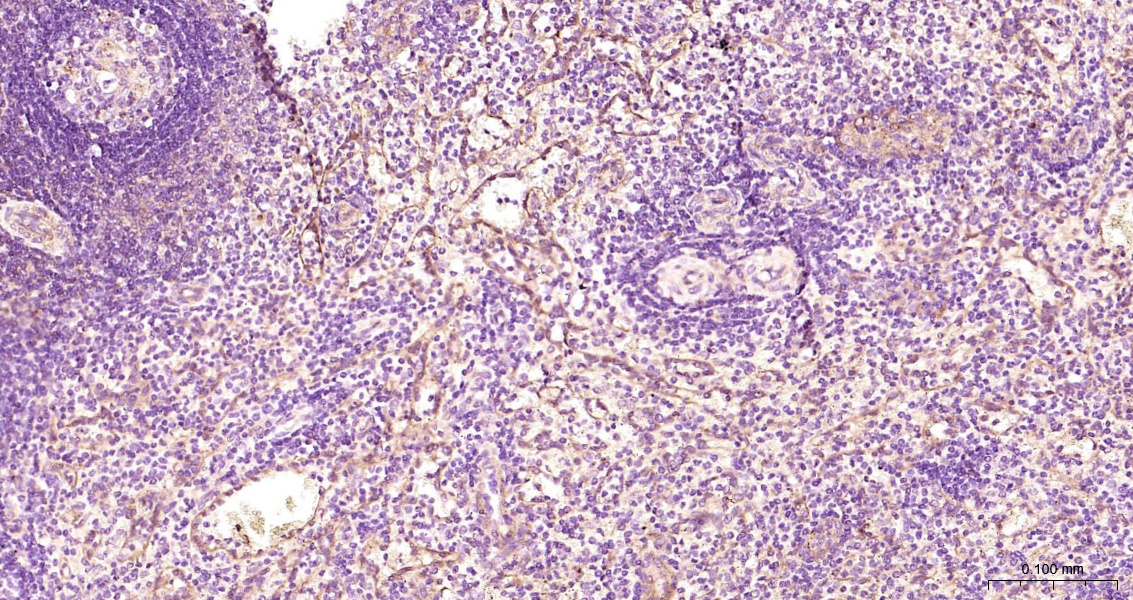

ZO-1 Monoclonal Antibody

Catalog # bsm-41327m

Product Name ZO-1 Monoclonal Antibody

Applications WB, ICC/IF

Reactivity Human

Background The N-terminal may be involved in transducing a signal required for tight junction assembly, while the C-terminal may have specific properties of tight junctions. The alpha domain might be involved in stabilizing junctions. Plays a role in the regulation of cell migration by targeting CDC42BPB to the leading edge of migrating cells.